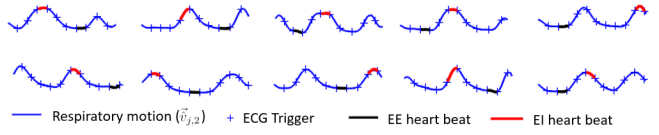

Table 1 summarizes the Pearson correlation coefficients for all the volunteers. The results show that the extracted respiratory signal has a high, positive correlation with the reference in all cases. This method is also robust across different respiratory patterns. Fig. 3 shows representative results from two volunteers, one with short respiratory cycles and the other with long cycles. As highlighted by the red arrow, this method is also tolerant of irregular motion. For some slices in Fig. 3, the difference between the reference and the proposed method is more pronounced. This is expected because the two methods measure different quantities: the proposed PCA-based method extracts the respiratory motion from the entire image, while the non-rigid image registration only tracks the motion in a small user-defined ROI.